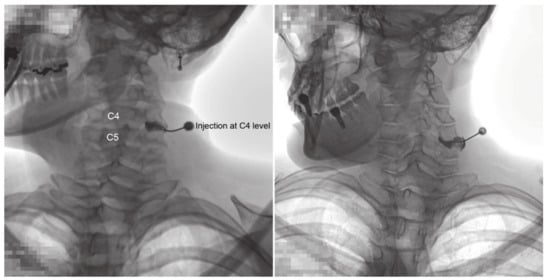

Fluoroscopic Findings of Extra-Cervical Facet Joint Flow and Its Incidence on Cervical Facet Joint Arthrograms

2.2. CFJ Injections/Arthrogram Analyses